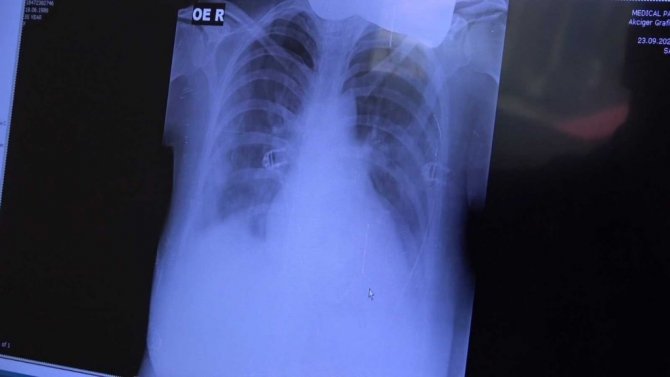

35 yaşında gebe bir hastanın akciğer filmindeki yoğun tahribatı gözler önüne seren Prof. Dr. Şevket Özkaya, "Bir hafta önce kovid semptomlar ile geldiğinde gerçekten akciğerleri çok kötüydü. 1 hafta içinde yaygın ARD vurgusu gelişti ve artık solunum yetmezliğinde bu hasta. Bunu hayatta tutmaya çalışıyoruz. Birkaç günümüz daha var. Tedavi ile düzelteceğiz. Lütfen gebelerimizin aşı olması gerekiyor. Özellikle kadın doğumcularımızın gebeleri aşılamaya yönlendirmelerini istiyoruz. Yoksa 35 yaşındaki bu hastamızın filmi gerçekten ürkütücü ve korkutucudur" şeklinde konuştu.

39 yaşında yeni doğum yapmış ve hamilelik sürecinde kovide yakalanmış bir hastanın akciğer filmini inceleyen Özkaya, "Birkaç günlük bebeğini bırakarak yoğun bakımda yatan bir anne. Bu anne de bebeğini düşünerek aşısını olmaktan korkmuş ama şu an yoğun bakımda yaşama mücadelesi veriyor" açıklamasında bulundu.